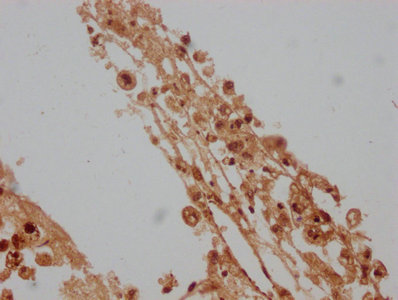

IHC image of CSB-PA012734LA01HU diluted at 1:100 and staining in paraffin-embedded human melanoma cancer performed on a Leica BondTM system. After dewaxing and hydration, antigen retrieval was mediated by high pressure in a citrate buffer (pH 6.0). Section was blocked with 10% normal goat serum 30min at RT. Then primary antibody (1% BSA) was incubated at 4°C overnight. The primary is detected by a biotinylated secondary antibody and visualized using an HRP conjugated SP system.

IHC image of CSB-PA012734LA01HU diluted at 1:100 and staining in paraffin-embedded human liver cancer performed on a Leica BondTM system. After dewaxing and hydration, antigen retrieval was mediated by high pressure in a citrate buffer (pH 6.0). Section was blocked with 10% normal goat serum 30min at RT. Then primary antibody (1% BSA) was incubated at 4°C overnight. The primary is detected by a biotinylated secondary antibody and visualized using an HRP conjugated SP system.